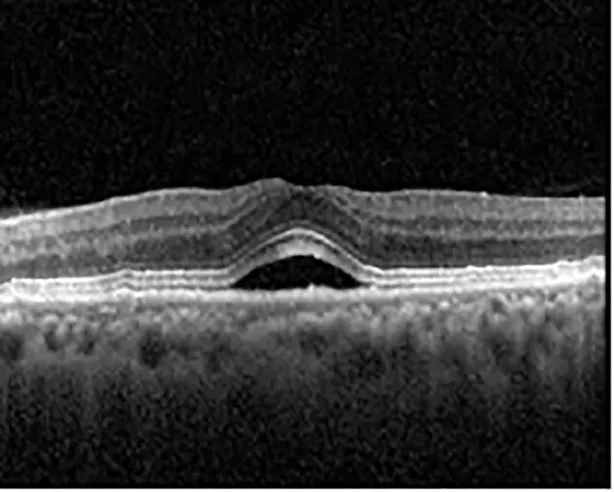

The patient began treatment with oral pemigatinib daily and was followed up for an ophthalmic examination during the second treatment cycle approximately 5 weeks into the treatment process. The patient had at this stage received 28 doses of 13.5 mg per day, which was administered in cycles of 14 on-days and 7 off-days, and had no visual or ophthalmic complaints. The non-corrected VA was OD 20/30 + 1 and OS 20/20. The OCT examinations revealed subfoveal SRF bilaterally. The fundus examination was otherwise unremarkable outside the patient’s prior documented peripheral drusen. Repeat autofluorescence was overall unchanged, though a slight hypofluorescent ring may be visualized in Figure 2. The current pemigatinib protocol recommendation for asymptomatic patients suggests no dose modification; however, with worsening presentation or positive symptoms, it is recommended to withhold pemigatinib. After discussion with the patient’s oncologist, it was decided to continue the medication at this time. Serial monitoring of the patient’s symptoms, vision, and SRF were conducted on specific days during active treatment cycles and days off-cycle to monitor the SRF. Subsequent evaluations demonstrated complete resolution of SRF while off-cycle, and asymptomatic re-accumulation of fluid while on-cycle with varying levels of VA. (Table 1) As we see demonstrated in the table below, in the later stages of the active cycles, such as day 13 of 14 of cycle 2, day 13 of 14 of cycle 3, day 13 of 14 of cycle 4, and day 14 of 14 on cycle 5, the patient’s VA showed no correlative changes based on the presence of SRF. The fluctuations in the patient’s VA certainly occurred, but were likely to be secondary to surface changes, as certain off-cycle days actually presented with lower acuities than days when the SRF was present on OCT examination.

Table 1

| Cycle, day, on/off | VA OD; OS | CMT OD; OS | OCT OD | OCT OS |

|---|---|---|---|---|

| Prior to initiation | 20/40; 20/20−2 | 274; 275 | ![]() | ![]() |

| Cycle 2, day 13/14, on | 20/30+1; 20/20 | 365; 355 | ![]() | ![]() |

| Cycle 2, day 4, off | 20/30−2; 20/20−2 | 282; 280 | ![]() | ![]() |

| Cycle 3, day 6/14, on | 20/40−1; 20/30−1 | 306; 301 | ![]() | ![]() |

| Cycle 3 day 13/14, Oon | 20/50+1; 20/30−2 | Poor tracing; 376 | ![]() | ![]() |

| Cycle 3, day 3, off | 20/30−1; 20/25 | 320; 329 | ![]() | ![]() |

| Cycle 3, day 10, off | 20/50−2; 20/30−1 | 269; 276 | ![]() | ![]() |

| Cycle 4, day 8/14, on | 20/50−2; 20/30 | 333; 317 | ![]() | ![]() |

| Cycle 4, day 13/14, on | 20/40−2; 20/25 | 360; 348 | ![]() | ![]() |

| Cycle 4, day 1, off (9/6) | 20/30; 20/25−1 | 273; 271 | ![]() | ![]() |

| Cycle 5, day 14/14, on | 20/30−1; 20/20 | 375; 364 | ![]() | ![]() |

| Cycle 5, day 6, off | 20/40+2; 20/30−2 | 276; 278 | ![]() | ![]() |

Highlights the visual acuity, central macular thickness, and the physical OCT of the macula for this patient in both the right and left eyes during various stages of the patient's chemotherapy treatment cycle.